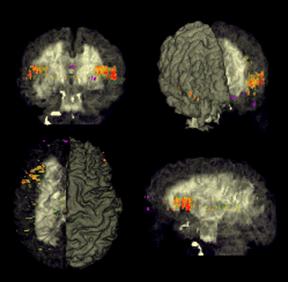

Tot nog niet zo lang geleden was het een mysterie wat

zich afspeelde in het menselijk brein. Moderne imaging technieken brachten

hierin de afgelopen jaren snel verandering. Met name imaging technieken als PET

(Positron Emission Tomography), MEG (MagnetoEncefaloGrafie)

en fMRI (functional

Magnetic Resonance Imaging) hebben een nieuwe impuls gegeven aan het

hersenonderzoek. Deze technieken brengen namelijk niet de anatomie van de

hersenen in beeld, maar de kleurrijke plaatjes geven de functie van de

verschillende hersengedeeltes weer.

Zulk inzicht wordt gebruikt voor wetenschappelijke en therapeutische

doeleinden. Inzicht in het functioneren van het brein zal het ook mogelijk

maken om beter te kunnen interveniëren in datzelfde brein. Zo is het nu

makkelijker het effect van psychotherapie en psychofarmaca te meten en te

verbeteren, hersenoperaties efficiënter uit te voeren en nemen de mogelijkheden

voor neurostimulatie en hersenprotheses hand over hand toe.

Localisatie van Hersenfuncties

In dit overzicht

kunt u zien dat de verschillende hersenlobben ieder een specifieke functie

hebben. Zo zijn er specifieke gebieden voor horen, zien, en bewegen. Ook het

spreken, en spraakverstaan kent aparte gebieden.